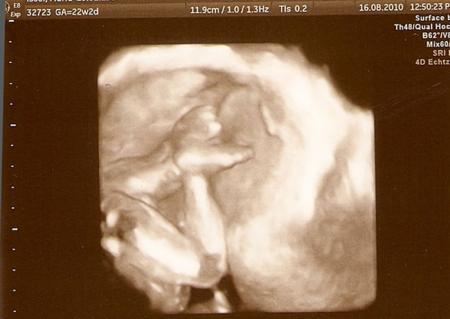

und einmal versteckt, Kopf mit Arm

Bild zu